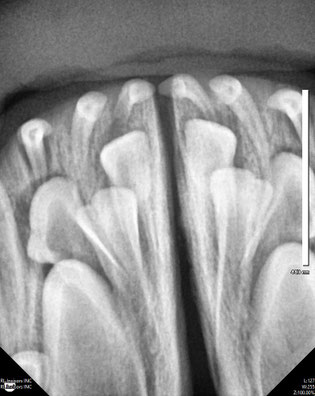

In den wenigsten Fällen geht es darum Zahnstein zu entfernen, da wit mit Hilfe des Dentalröntgens Zahnpatholigien erkennen, die in der klnischen Untersuchung verborgen bleiben. So ist es neben der Inhalationsnarkose ein fester Bestandteil jeder Zahnbehandlung. Bei 30-40% der klinisch gesund aussehenden Zähne verstecken sich defekte von Kieferknochen oder Zahnwurzel, die ohne eine Röntgenaufnahme nicht gefunden werden können.